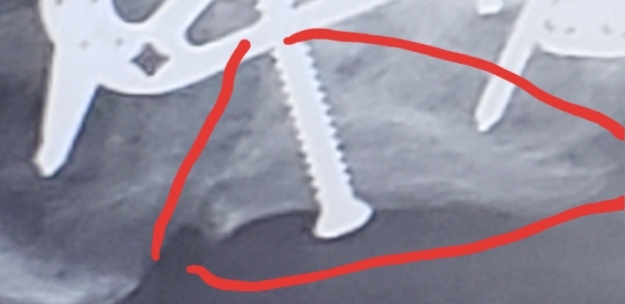

Hi Jeff ,man hope u get better soon,one question why u doc put the long screw that way in first place ,maybe he mest up the using too long siize of it...... doctors... |

pete petem75 wrote: Hi Jeff ,man hope u get better soon,one question why u doc put the long screw that way in first place ,maybe he mest up the using too long siize of it...... doctors... I think that pin was the only way to securely hold this broken portion of calcaneus back to itself. You seem skeptical about the doctors, how come buddy? |